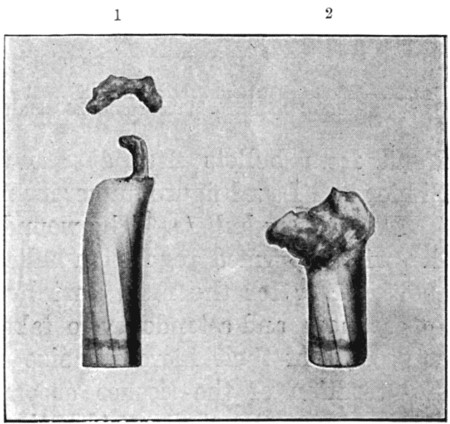

40. Mauser Bullet, Jeffreys-Tweedie Modification94

41. Section of Mark IV. and Soft-nosed Mauser94

42. Tampered Bullets95

43. Large Leaden Sporting Bullets98